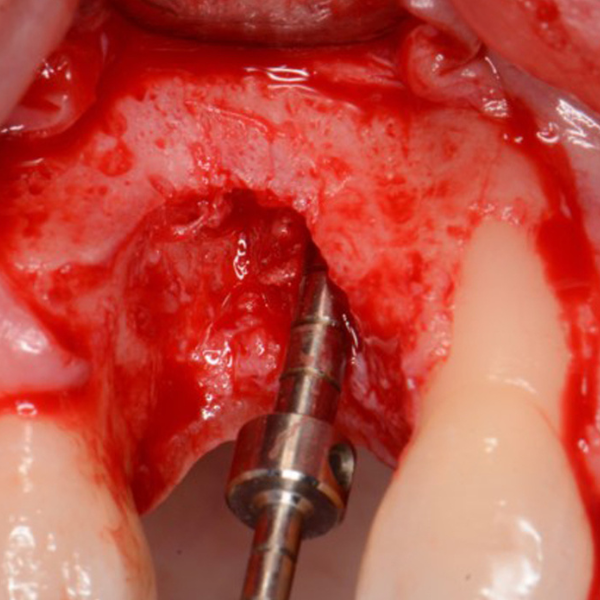

Anterior Implant Placement & Graft